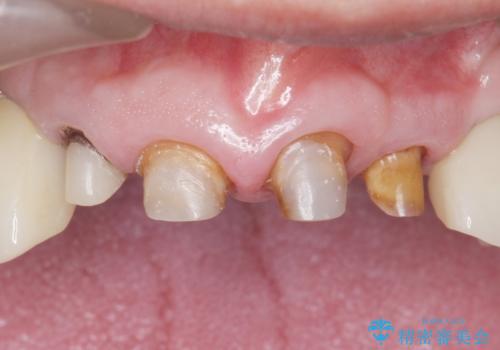

- 前歯の被せ物がとれたまま放置されていた患者様です。

前歯4本のうち3本の被せ物が脱離し、残りの1本の被せ物は劣化し変色していました。

古い被せ物や土台・虫歯をしっかり除去したのち、セラミック治療を行いました。

患者様のご希望により、根尖病変の明らかな左上2のみ根管治療を行いました。

- ¥610,000 (根管治療×1本、土台×4本、仮歯×4本、クラウン×4本)費用は治療当時の料金となります